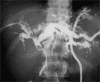

Background: Caroli's disease (CD) is a benign congenital disorder characterized by segmental cystic dilatation of the intrahepatic biliary ducts. Therapeutic strategy includes medical treatment, percutaneous, endoscopic or surgical drainage of the affected bile ducts, liver resection or transplantation. The aim of this study was to analyse the results and long-term follow-up of a consecutive series of patients who underwent surgical treatment for CD.

Results: The average age of the patients was 45.8 years. Recurrent cholangitis was the main clinical manifestation (70%). In unilateral CD a liver resection was performed in nine patients (left lateral sectionectomy in seven, left hepatectomy in one and right hepatectomy in one). In bilateral disease a cholecystectomy, duct exploration, hepaticojejunostomy and liver biopsy of both lobes were performed. Average follow-up was 60 months. All the patients are alive and free of symptoms without recurrence in the remnant liver.